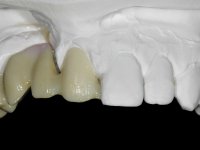

Fixed partial denture between teeth 15 and 11, using teeth 14, 13 and 11 as abutments. Teeth 12 and 15 were planned as ovoid pontics. The framework material chosen was zirconia and the veneering ceramics should have a gum-shade component to rehabilitate the soft-tissues.

After the root canal treatment of tooth 11, dental impressions were taken to do a fixed provisional (reinforced) acrylic prosthesis. The provisional bridge included an acrylic component with a gum-shade color, to evaluate the integration of the treatment plan, in relation to function and esthetics. The preparation of teeth 14 and 13 were minimal invasive, with supra-gingival finishing lines, preserving enamel at its uttermost. Tooth 11 was prepared in a conventional way, with an intra-sulcular margin. The provisional bridge was rebased intra-oral with an autopolymerized acrylic. After 4 weeks, a dental impression with a double mixture technique was done. In the dental lab, CAD-CAM technology was used to produce a zirconia framework. In the provisional bridge, it was noted by the patient, and by ourselves, the need for symmetry in the dimensions and shape of the teeth, in relation to their homologues of the 2nd quadrant. Accordingly, a mirror effect was selected in the CAD design of the framework, to mimic in the prosthetic structure the dimensions and shape of the homologous natural teeth. Framework design included also a small zirconia wing covering the palatal surface of the non-prep tooth 21. This wing serves as an additional support and, simultaneously, avoids an eventual occurrence of a future diastema between central incisors. Color selection of teeth and soft-tissues was done by the ceramist in the dental office. After evaluation and approval of the prosthetic work placed in mouth, the dental bridge was bonded. This bonding procedure was optimized by the addition of a zirconia liner in the inner surface of the framework and in the internal surface of the wing. This treatment proved to be esthetically acceptable and functionally able, with a strong contribution to the patient’s self-esteem.